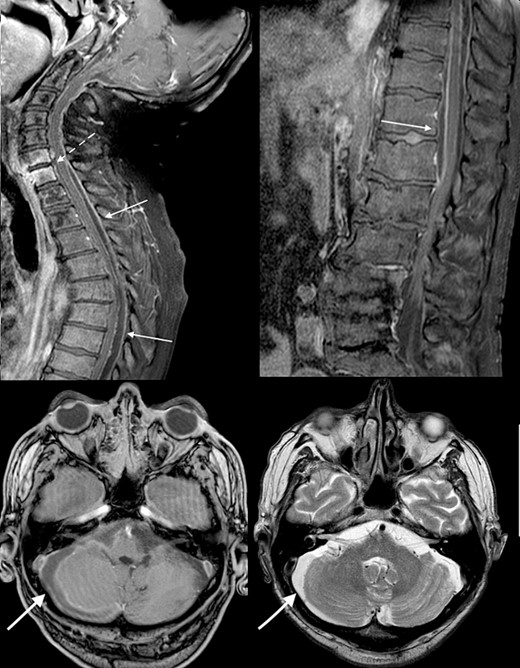

The patient became progressively obtunded, requiring intubation and ventilation in the Intensive Care Unit. Bacterial culture results demonstrated colonization with multiple microorganisms including Staphylococcus aureus, Candida albicans, Proteus mirabilis, Klebsiella pneumoniae, Serratia marcescens, and Lactobacillus species. This prompted the modification of antimicrobial coverage to Ceftazidime-Avabactam, Daptomycin, Metronidazole, and Vancomycin. Repeat imaging 10 days after presentation showed progression to diffuse cerebritis and pyogenic ventriculitis (Fig. 4). A multidisciplinary meeting was held with the patient’s next-of-kin and the decision was to provide comfort measures in light of the overall clinical picture, progression of infection, and existing poor patient performance status. The patient passed away peacefully in the presence of his family 13 days following his admission.

Diffusion-weighted MRI-brain showing intensely high signal in cerebral cortex (arrow) and ventricles (arrow) consistent with infective cerebritis and ventriculitis.